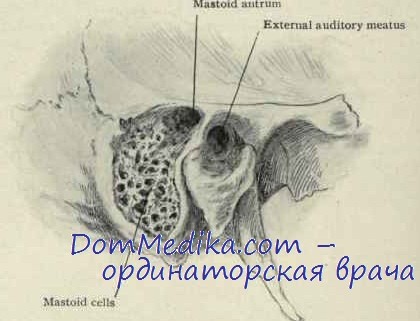

Анатомия сосцевидного отростка